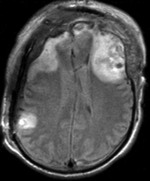

unregistered exam 1 & 2

Exam 2 aligned to Exam 1 (affine only)